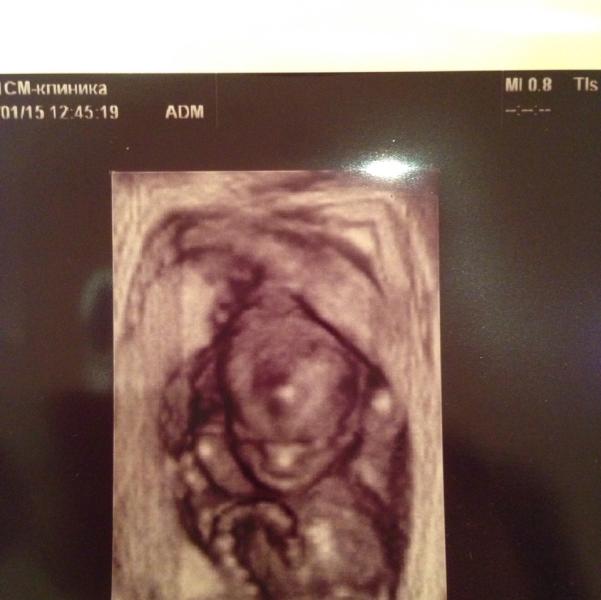

Сходила на скрининговое узи второго триместра) у меня в платной его уже назначили. В общем, всё хорошо, выяснили что мой малыш очень активный и акробат) он хотел писать и зевал)

ну а еще, что на 80% (она на всякий случай оставила 20 на ошибку) это МАЛЬЧИК, но по-моему она просто перестраховалась, там было очевидно) сначала прикрывал ногами и пуповиной, а потом повернулся и оп пуповина отдельно, а там огого между ног))) подарила мне 3D фото моего мальчонки с руками за головой)